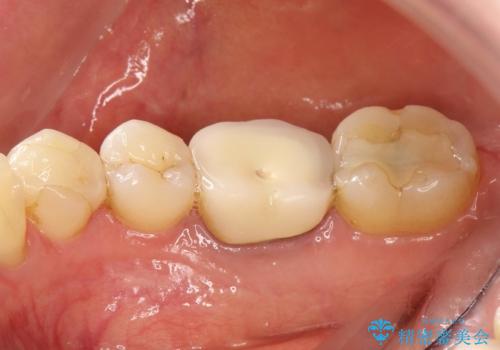

咬んだ時の違和感 顕微鏡で発見された歯の穴を処置し、かみ合わせを回復する

- 再根管治療にて発見されたパーフォレーションを修復し、改めてかぶせ物を製作する。

かぶせ物の種類:Bellezza